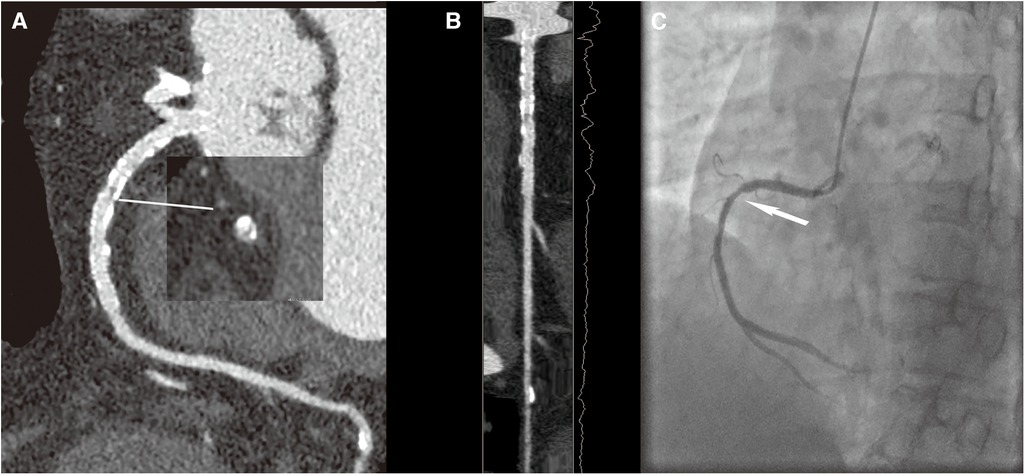

Previous studies have shown that CCTA was the first-line non-invasive imaging technique in patients with suspected coronary artery disease and ICA remained the standard reference method for the identification and characterization of coronary artery stenosis. When anatomical coronary narrowing >50% on ICA was considered a reference standard, CCTA had a specificity of 78%. CCTA with high-resolution CT could achieve a specificity of 88% in a per-vessel analysis compared with ICA in patients with high calcium scores provided promising preliminary data demonstrating a high diagnostic accuracy with a specificity of 88% in a per-vessel analysis compared with ICA (28, 29). In our study, in agreement with previous studies, the specificity values were 77.9% for the SD group and 94.2% for the LD group in a per-vessel analysis compared with ICA for patients after PCI. Our results were coordinated with the finding of the previous study that the high-resolution mode CCTA protocol could decrease the false-positive findings than the traditional mode CCTA (28). Furthermore, we have noticed that the diagnostic accuracy and PPV for ISR in the LD group were higher than those in the SD group, which proved that compared with the traditional iterative reconstruction in combination with SSF1, CCTA images of DLIR and SSF2 technologies had better diagnostic performance on ISR with better noise containment and motion correction capability. Specifically, the accuracy and PPV of ISR diagnosis were 10.4% and 19.3% higher for the LD group than those for the SD group. We further reviewed the misdiagnosed 23 cases, 15 (4 for the large-caliber stent subgroup and 11 for the small-caliber stent subgroup) were misdiagnosed in the SD group, and only 8 (1 for the large-caliber stent subgroup and 7 for the small-caliber stent subgroup) were misdiagnosed in the LD group. We noticed that the misdiagnosed rates of the SD group were higher than those of the LD group. We have found that all the misdiagnosed 23 cases were overestimation of luminal stenosis, which we speculate is the combination of heart motion, excessive calcium plaque load, small stent size, and particularly the still limited spatial resolution of the CT systems. However, the fact that the LD group had a much lower misdiagnosis rate and that the LD group with SSF2 provided much better performance on the visibility of luminal stenosis (Figures 4, 5) demonstrated the importance of motion correction in providing accurate IRS diagnosis for patients after PCI.

Figure 4

Figure 5